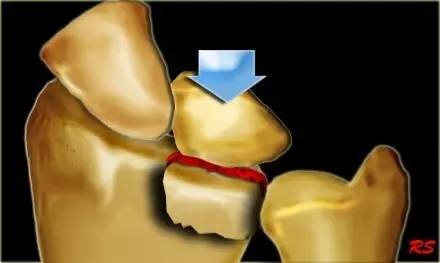

6. Hahn-steinthal 骨折

全肱骨小头骨折,为一种少见的关节内骨折,多见于成年人。常由于跌倒时手过度伸直或在屈肘时因桡骨小头撞击肱骨小头,并同时有外翻力存在时发病,亦可伴有滑车骨折与内侧副韧带的撕裂。X 线表现为全肱骨头骨折,向上移位。

Hahn-steinthal 骨折 X 片(来源:Hahn-Steinthal fracture: a case report.BioMed central Cases Journal20081:239)

Hahn-steinthal 骨折 CT 片(来源:Hahn-Steinthal fracture: a case report.BioMed central Cases Journal20081:239)